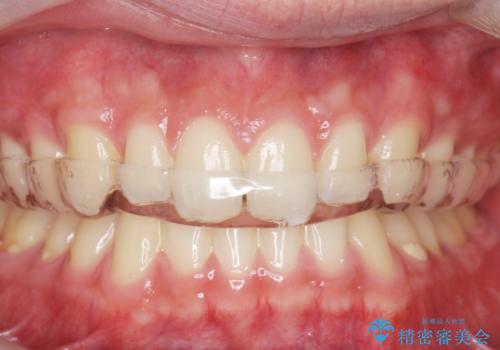

ナイトガードで歯ぎしり予防

- 歯ぎしりが気になるとの事で来院。

しっかりしたナイトガードが欲しいとの事だったので自費のナイトガードのご案内をしました。

ナイトガードは夜寝ている時、無意識に歯ぎしりをして歯がすり減ることを防ぐことがあります。また、歯が割れたり欠けたりするのも防いでくれます。